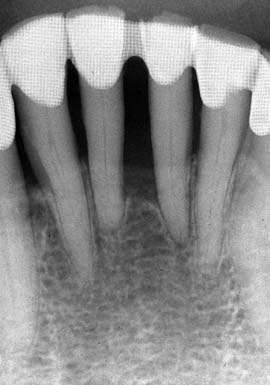

(図4)32年経過(2007年3月5日)、70歳。十分機能している